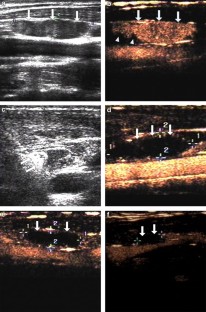

Fig. 1

Fig. 2